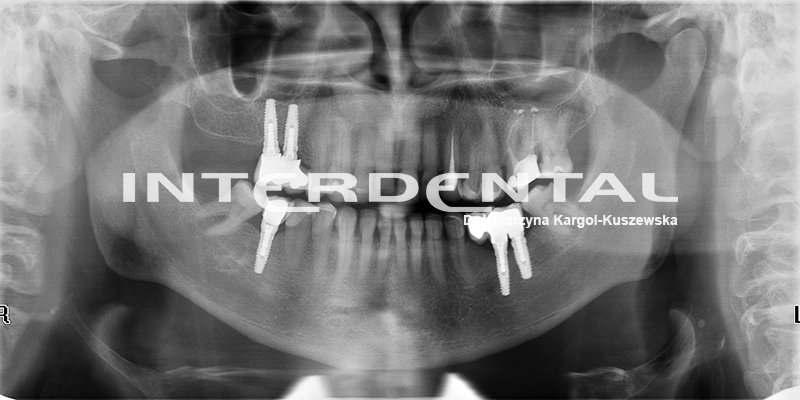

Zdjęcie pantomograficzne jest to zdjęcie rentgenowskie przeglądowe. Przedstawia ono ogólny stan uzębienia oraz przyległych struktur anatomicznych są to: kości szczęki i żuchwy, stawy skroniowo-żuchwowe, częściowo zatoki szczękowe, kostne dno jamy nosowej, oczodołów, etc.

Pantomogram wykonywany okresowo pozwala ocenić skuteczność procedur leczniczych, zlokalizować nieprawidłowości, które w sposób bezobjawowy rozwijają się w obrębie wyżej wymienionych struktur twarzoczaszki. W połączeniu z badaniem klinicznym jest niezastąpionym i cennym źródłem informacji dla lekarza prowadzącego.

W Klinice Interdental wykonujemy badania pantomograficzne w oparciu o urządzenia cyfrowe, które w przeciwieństwie do tych starszej generacji-zwanych analogowymi, emitują bardzo niską dawkę promieniowania od 5-20 μSv. Urządzenia cyfrowe redukują dawkę potrzębną do wykonania badania nawet o 70%.

Uzyskany obraz jest niezwykle dokładny.